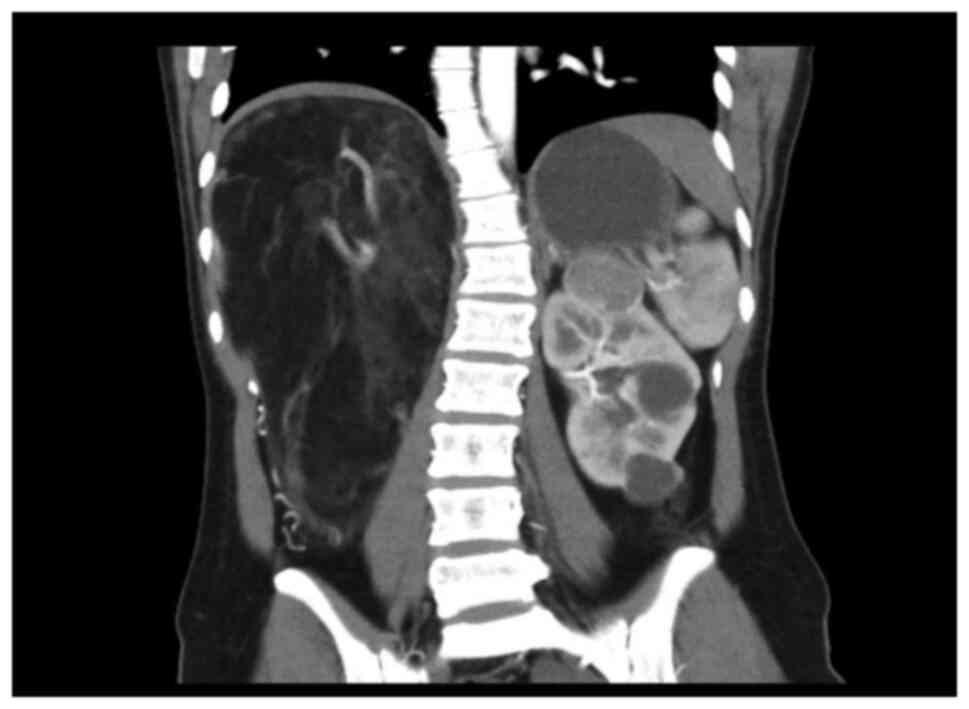

The 20-year-old young female patient has been diagnosed with epilepsy since childhood and has been treated with valproate sustained release tablets. She was admitted to the department of neurology of our hospital due to repeated daze, occasionally accompanied by nausea, vomiting, and hallucinations. Physical examination showed that the patient was slightly slow in response and expression, and her calculation was poor. Multiple small papules and nodules can be seen on her cheeks. Palpation of the right upper abdomen revealed a tough mass with smooth surface, fixed position, and no tenderness. Valproic acid test in the laboratory showed that the patient's CYP2C9 genotype was CYP2C811, and the enzyme activity was fast metabolism (EM) type. POLG (A467TG>A) was of wild homozygous type, POLG (W748SC>G) wild homozygous type SLCO1B1 genotype was 1b1b, and ApoE genotype was E2E4. The electrolyte, liver enzymes, renal functions, cardiac functions, routine examination of blood and urine, and coagulation functions were normal. Abdominal enhanced CT scan showed that the liver was obviously pushed, and the spine was scoliotic. A huge mass occupied the right upper quadrant, with a size of ~236x125x149 mm. The CT value was about-78HU. Blood vessels could be seen inside, and the boundary between the blood vessel and the kidney was unclear. The surrounding tissue was pushed, and the right kidney was displaced to the middle abdomen (Fig. 1). Moreover, two inhomogeneous enhancement nodules were present in the middle and lower pole of the right kidney. The larger nodule (26x33 mm in size) was in the right kidney. Multiple low-density shadows with no enhancement were also evident in the right kidney. In the left kidney, an inhomogeneous enhancement nodule was present on the upper pole, and its size was 28x29 mm. Multiple no enhancement low-density shadows (Fig. 2) were distributed in the left kidney. The right adrenal gland was unclear. The shape, size, and density of the left adrenal gland were normal. No obvious dilation and hydrops were observed in the bilateral renal pelvis and calyces, and the intestinal curve was pushed. No obvious enlarged lymph nodes and no ascites signs were seen behind the peritoneum. The result of the Chest CT scan showed multiple nodular shadows with sizes of ~2-3 mm in the right upper lobe and dorsal right lower lobe. A nodular shadow, ~3 mm in size, was seen under the pleura of the tongue of the left upper lobe. Cranial MRI showed the following results. Abnormal signals were detected from the bilateral cerebral hemisphere cortex, right putamen, and right caudate nucleus. A slightly low signal was observed in T1WI. A slightly high signal was observed in T2WI and FRAIR. The DWI showed no diffusion with limited high signal. Under the bilateral maxillary sinus mucosa, round-like long T1 long T2 signal shadows were seen, and the larger one was ~15x17 mm in size. Considering the patient's medical history and the results of laboratory examination, the diagnosis included epilepsy, giant hamartoma of the right kidney, hamartoma of the left kidney, multiple pulmonary nodules, and abnormal head signals, which were highly consistent with the manifestations of TSC. Although the patient had no obvious symptoms of abdominal visceral compression, and laboratory examination showed no obvious abnormalities in the kidney function. The compression of a huge abdominal mass caused the liver and kidney to deviate significantly and led to spine scoliosis. The continued growth of the mass may affect the function of the kidney and the digestive system. Moreover, the overgrown mass puts the patient at risk of spontaneous rupture and bleeding, which are life-threatening. So, the mass was indicated for surgical resection. After comprehensive preparation before the operation, the patient underwent open mass resection and right kidney partial resection. The appearance of the tumor is shown below (Fig. 3). Postoperative pathological results (Fig. 4) confirmed RAML, and the immunohistochemical results were as follows: HMB45 +, SMA +, Des +, S100 +, and Ki67 (1% +) (Fig. 5). The patient recovered smoothly after the operation. No recurrence of kidney tumors was found. Nodules in the lungs and abnormal head signals remained the same after the half-year follow-up period.

Figure 2

Multiple no enhancement low-density shadows are distributed in the left kidney.